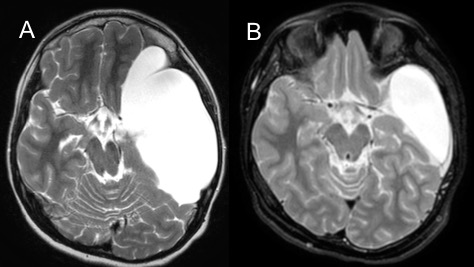

les kystes sylviens

c’est le traitement de choix lorsque le kyste fait face au plan vasculaire.

elle consiste à fenêtrer la paroi interne du kyste de part et d’autre de la carotide, et si possible en avant du nerf optique.

étant donné l’exiguïté de l’abord et les rapports vasculaire étroits, il vaut mieux éviter d’utiliser un ballon.

les complications sont essentiellement marquées par les collections sous-durales, surtout chez le jeune enfant, qui peuvent se compliquer de fistulisation cutanée.